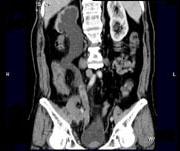

问题 男,73岁,无痛性全程血尿2个月余,CT检查如图所示,下列说法正确的是 ( )

选项 A、考虑为右侧输尿管中下段癌合并膀胱癌 B、考虑为右侧输尿管及膀胱结核 C、膀胱内可见宽基底的软组织肿块影 D、右肾及输尿管上段扩张积水 E、右输尿管中下段可见沿输尿管走行的长约10.6cm,不规则的软组织肿块影

答案 ACDE